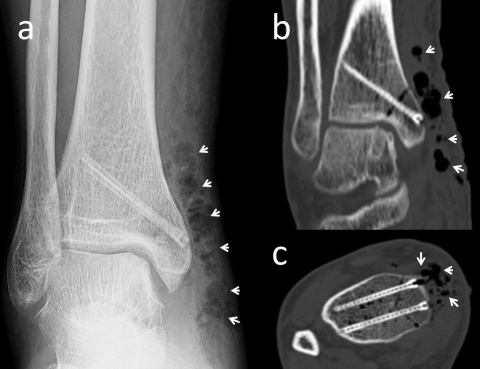

In Bezug auf die Gasbildung und Resorption zeigt die Computertomographie ähnliche Ergebnisse wie die konventionellen Röntgenaufnahmen. In der Frühphase sind sowohl die Schrauben als auch die umgebenden Gasansammlungen deutlich sichtbar (Abbildung 5). Langfristige CT-Untersuchungen zeigen, dass das Gas vollständig resorbiert wird und damit vollständig verschwindet. Die Schrauben sind bis zu ihrer Umwandlung in kortikales Knochengewebe deutlich erkennbar (Abbildung 6). Adil et al. haben nachgewiesen, dass diese Konturen vier Jahre nach der Implantation in der tomographischen Dichtemessung ähnliche Hounsfield-Einheiten aufweisen wie die umgebende Kortikalis (17). Darüber hinaus erzeugen Implantate auf Magnesiumbasis – im Gegensatz zu konventionellen Metallimplantaten wie Titanschrauben – nur minimale Metallartefakte (18-20). Für die Nachbeobachtung der Patienten stellt dies einen signifikanten Vorteil dar.

Magnesiumschrauben fixiert wurde. (a) In der anterior-posterioren

Röntgenaufnahme des Knöchels in Monat 30 nach der Operation sind

die Heilung der Fraktur und die Umrisse der Schrauben sichtbar. (b)

Koronare und (c) axiale CT-Aufnahmen weisen keine Gasansammlung

im Knochen auf und die Schrauben zeigen eine ähnliche Dichte wie die

umgebende Kortikalis.

Läsion am Talus einer Innenknöchel-Osteotomie und Mosaikplastik

unterzogen wurde. Die biplanare Innenknöchel-Osteotomie

wurde mit zwei Magnesiumschrauben fixiert. (a) Die anterior-posteriore

Röntgenaufnahme des Knöchels am 7. postoperativen Tag zeigt an

der Operationsstelle diffuse Gasansammlungen im Weichgebe (weiße

Pfeile). (b) Koronare und (c) axiale CT-Aufnahmen mit sichtbarem Gas

(weiße Pfeile).